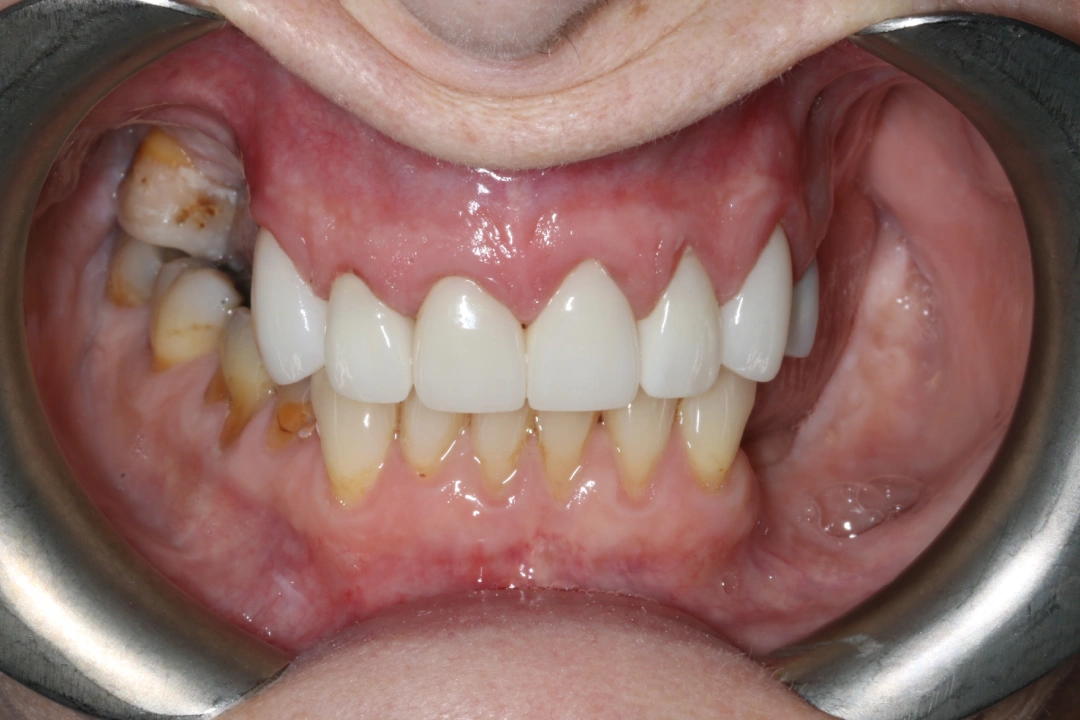

Seven porcelain crowns were placed on her upper teeth as the first phase of treatment. Second phase of treatment is to replace her back teeth. The results are amazing and Naomi is ecstatic with her new smile

After